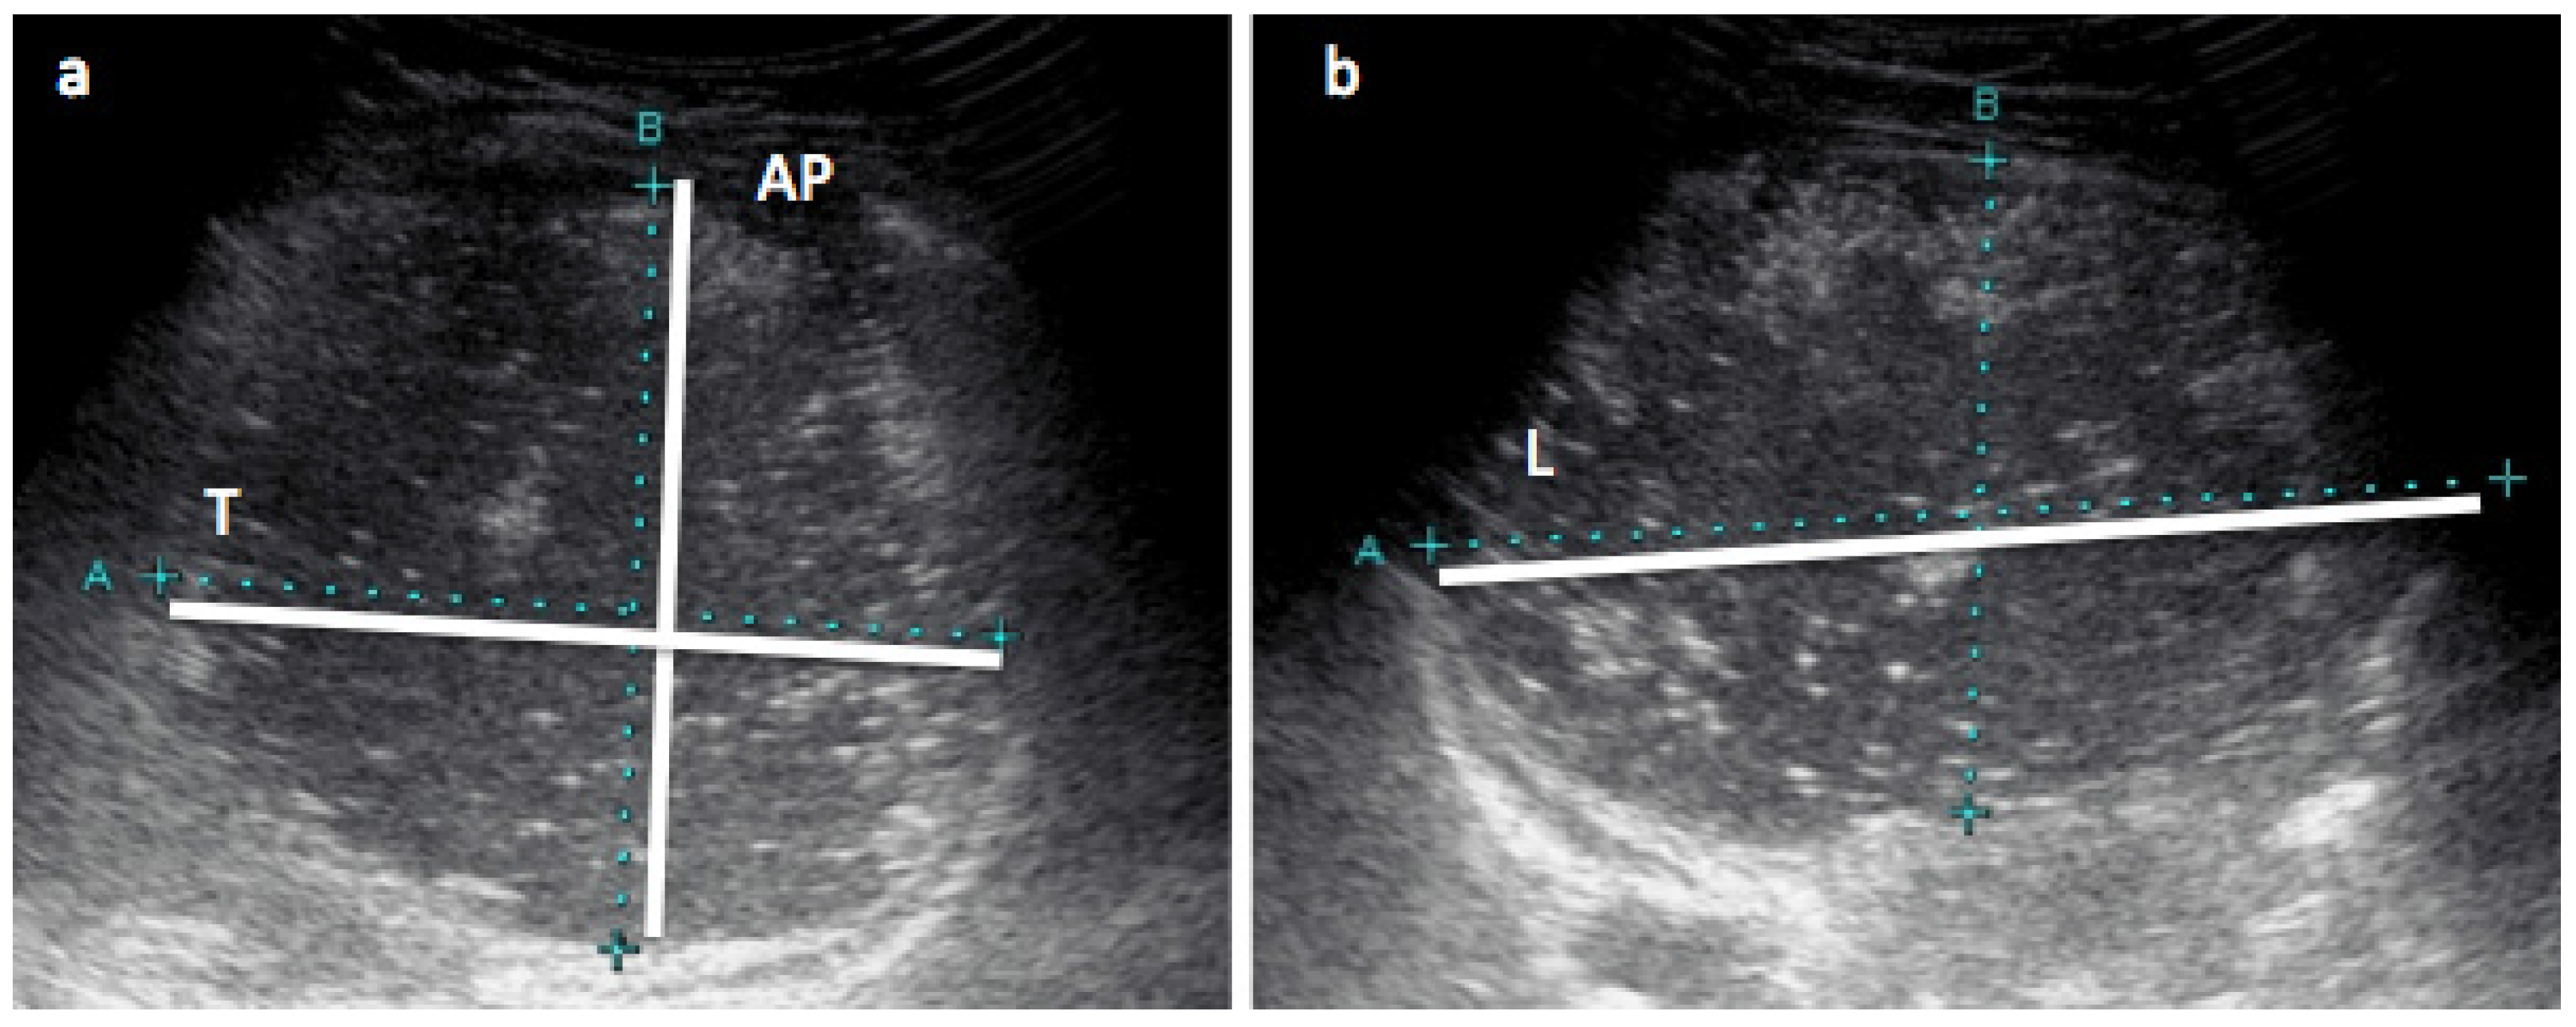

2.5. Stomach Measurements with Ultrasound

- Perrella, S.; Hepworth, A.; Simmer, K.; Geddes, D. Validation of ultrasound methods to monitor gastric volume changes in preterm infants. J. Paediatr. Gastroenterol. Nutr. 2013, 57, 741–749. [Google Scholar] [CrossRef] [PubMed]